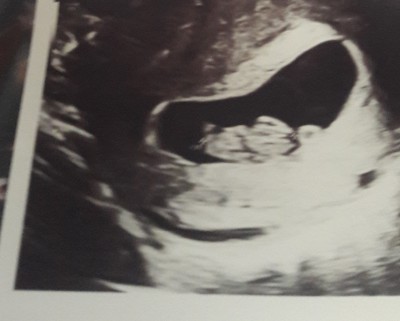

Kizlar bnde burda ogrndm ya  boyle bisi varmi merk etim şuan9+1 haftaligm sizce ne

image

Hadi ya :) saglikla gelsinde  esim erkek diyo bn kiz baz kararm dgsiyor erkek diyrm

Kiz yok burda cogu kisi okudum kese yuvarlik kiz  fasulye gibise erkek mis ama bilmiyorumki bnde dedm paylasim bakim